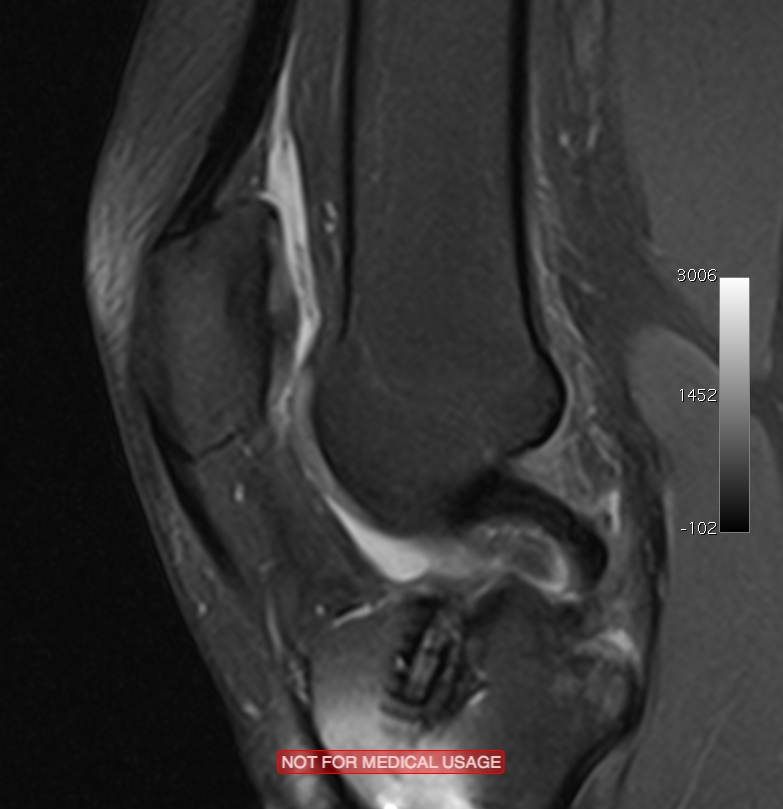

Typical MRI appearance of an osteochondral defect in the knee (a Knee Cartilage Defect Articular cartilage defects of the knee comprise of a spectrum of disease entities from single, focal defects to advanced degenerative disease of. Cartilage damage is most frequently seen between the ages of 15 and 30 or above the age of 50. Both types of knee cartilage can get torn and may cause symptoms like knee pain, buckling of the knee. Knee Cartilage Defect.

From ar.inspiredpencil.com